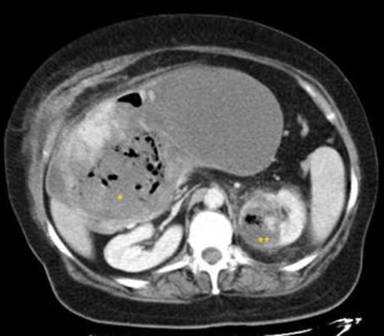

The postoperative course was uneventful and the patient underwent chemotherapy (3 cycles of adriamycin followed by 6 cycles of gemcitabine) for malignant fibrous histiocytoma, showing no response. The patient died 25 months after diagnosis due to local progression of the inflammatory pseudotumor, with no evidence of metastasis. Progressive alimentary intolerance conducted to an extreme cachexia. Finally, she died from acute sepsis because of infection of the tumoral necrosis (Figure 5).

Figure 5. Abdominal CT showing extensive tumoral necrosis. Gas inside the tumor (*) and in the left kidney (**) was considered a sign of severe infection. |